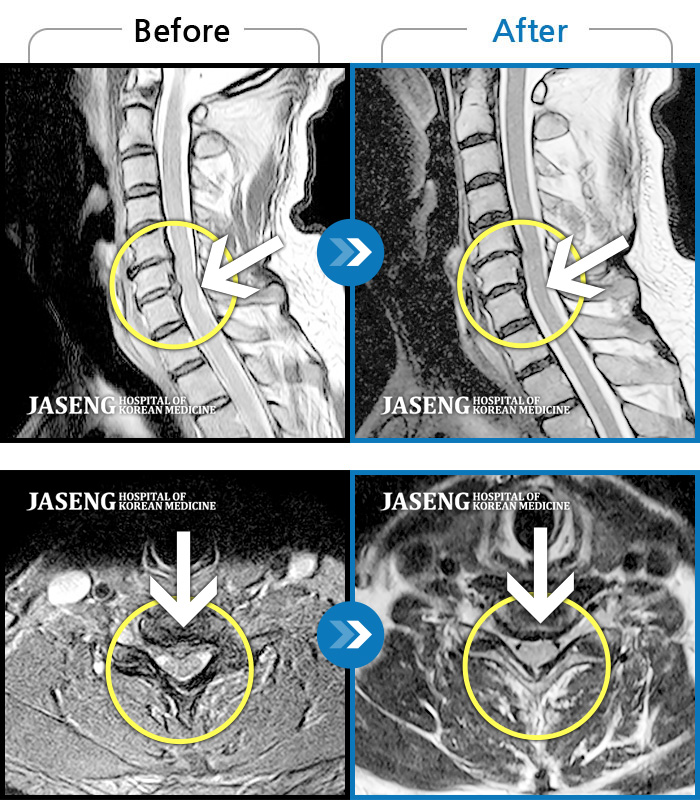

ȯںп Ǹ ǿ ԿǾ, ο ġ ۿ Ƿ ġḦ Ͻñ ٶϴ.